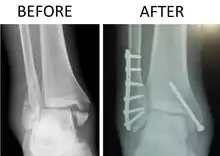

X-ray of trimalleolar fracture repair before and after ORIF surgery

Surgical repair using open reduction and internal fixation is generally required, and because there is no lateral restraint of the foot, the ankle cannot bear any weight while the bone knits. This typically takes six weeks in an otherwise healthy person, but can take as much as twelve weeks. Non-surgical treatment may sometimes be considered in cases where the patient has significant health problems or where the risk of surgery may be too great.[1]